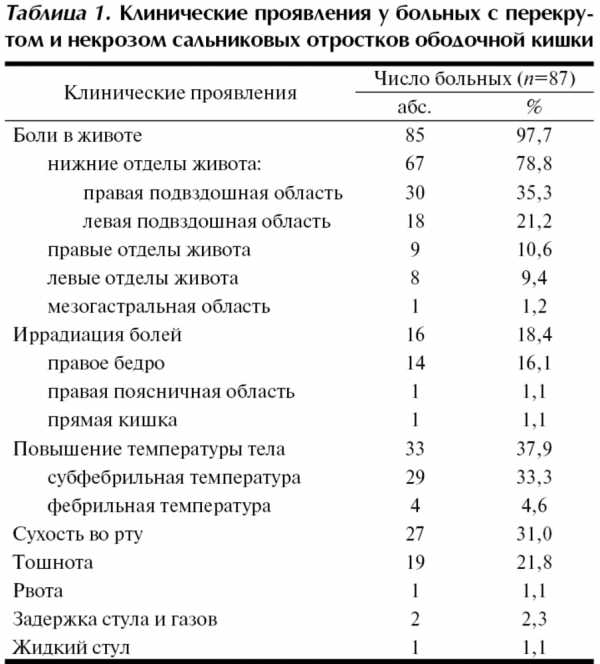

Диагностика в стационаре на дооперационном этапе базировалась на жалобах больных, данных анамнеза, физикального обследования, данных лабораторных и инструментальных методов исследования. Клинические проявления перекрута и некроза отростков были скудными и неспецифичными, что приводило к постановке ошибочного диагноза на дооперационном этапе у большинства больных. Основные клинические проявления у пациентов с перекрутом и некрозом отростков приведены в табл. 1.

Ведущим симптомом были постоянные боли в животе, отмечавшиеся у 85 (97,7%) больных. Преимущественной локализацией болей были нижние отделы живота — у 67 (78,8%) больных, часть из них отмечали локальные боли в правой или левой подвздошной области (см. табл. 1). У 7 (8,0%) больных имел место симптом Кохера-Волковича. Иррадиация болей присутствовала у 16 (18,4%) пациентов, чаще в правое бедро. Объяснить возникновение иррадиации болей у этих больных интраоперационными данными не удалось, лишь у 8 из них некротизированные отростки были спаяны с окружающими органами и тканями — стенкой толстой кишки, соседними отростками, большим сальником, париетальной брюшиной или придатками матки. У 14 (16,1%) больных боли усиливались при движении.

При выяснении данных анамнеза 7 (8,0%) больных отмечали наличие провоцирующих факторов: тяжелой физической нагрузки (3), резкого движения (1), приема антибактериальных препаратов (1), пищи (1), алкоголя (1). 26 (29,9%) больных самостоятельно принимали различные лекарственные средства (спазмолитики, анальгетики, антибактериальные препараты), которые не купировали болевой синдром. Неэффективность самостоятельного приема лекарственных препаратов и нарастающая интенсивность болей заставляли больных обращаться за медицинской помощью.

Жалобы на сухость во рту предъявляли 27 (31,0%) больных, на тошноту — 19 (21,8%). Рвота и нарушения стула отмечались у единичных больных. Лихорадкой страдали 33 (37,9%) пациента, чаще с подъемом температуры тела до субфебрильных значений. Нехарактерные жалобы были у 4 пациентов, что заставляло врачей заподозрить другое заболевание и приводило к постановке ошибочного предоперационного диагноза. С учетом данных интраоперационной лапароскопической картины возникновение жалоб можно связать с наличием сочетанных заболеваний, а также с развитием инфильтрата вокруг некротизированного отростка. 2 пациентки предъявляли жалобы на головокружение (интраоперационно, помимо заболевания отростка, обнаружены напряженная киста желтого тела у 1 и цистаденома левого яичника и маточная беременность 5 нед у 1). У одной пациентки были мажущие кровяные выделения из половых путей в течение 11 дней (интраоперационно диагностирован наружный эндометриоз малого таза). Один пациент предъявлял жалобы на учащенное мочеиспускание с резями над лоном (интраоперационно обнаружен плотный инфильтрат вокруг некротизированного отростка, вовлекающий большой сальник, стенку сигмовидной кишки, соседние отростки и фиксированный к париетальной брюшине в области дна мочевого пузыря).

Состояние 81 (93,1%) больного оценивалось как удовлетворительное, 5 (5,8%) — средней тяжести, 1 (1,1%) — тяжелое. Степень тяжести у последних 6 пациентов была связана с наличием сочетанных заболеваний — острого гангренозно-перфоративного аппендицита (1), перфорации дивертикула левой половины ободочной кишки (1), сопутствующих заболеваний терапевтического и неврологического профиля (4). Следует отметить, что 50 (57,5%) больных имели избыточную массу тела, в том числе предожирение выявлено у 13 (15,0%) пациентов, ожирение I степени — у 29 (33,3%), ожирение II степени — у 6 (6,9%), ожирение III степени — у 3 (2,3%). Средний индекс массы тела больных с перекрутом и некрозом отростков составил 29,7±5,0 кг/м2.

Основные данные, полученные при физикальном обследовании и лабораторно-инструментальных методах исследования, представлены в табл. 2.

Язык был влажным у 79 (90,8%), светлый налет на языке отмечался у 60 (69,0%) больных. При осмотре живот у всех больных был симметричным, притупления в отлогих местах живота не было обнаружено ни у одного пациента. Живот был вздут у 5 больных. У большинства пациентов перистальтика была обычной звучности, лишь в 4 наблюдениях отмечалось ее ослабление, у 2 из этих больных интраоперационно обнаружен местный фибринозно-гнойный перитонит.

Локальное напряжение мышц передней брюшной стенки обнаружено у 15 (17,2%) больных.

В большинстве наблюдений — 83 (95,4%) — отмечалась болезненность при пальпации живота, нередко локальная — у 52 (59,8%) больных. Области, в которых выявлена максимальная болезненность при пальпации живота, представлены на рисунке. Рисунок 1. Болезненность при пальпации живота.

Рисунок 1. Болезненность при пальпации живота.

В 77 (88,5%) наблюдениях болезненность при пальпации обнаруживалась в нижних отделах живота, из них в 44 (50,6%) максимальная болезненность выявлена в правой подвздошной области, в 29 (33,3%) — в левой подвздошной области. Симптомы острого аппендицита (Ровзинга, Ситковского, Воскресенского) были обнаружены у 31 (35,6%) больного, что приводило к постановке диагноза острого аппендицита на дооперационном этапе в этих наблюдениях. Во время лапароскопии лишь у 3 из них выявлен острый аппендицит: флегмонозный — у 2, гангренозно-перфоративный — у 1. Симптом Щеткина-Блюмберга от сомнительного до положительного обнаружен у 29 (33,3%) пациентов.

Пальпируемое образование в брюшной полости обнаружено у 3 больных. Интраоперационно у них выявлены рыхлый инфильтрат, состоящий из петли сигмовидной кишки, правой маточной трубы, сальниковых отростков сигмовидной кишки (1), перекрут двух отростков сигмовидной кишки между собой (1), спаянный с париетальной брюшиной отросток сигмовидной кишки (1).

Существенные диагностические трудности на дооперационном этапе встретились у одной больной, предъявляющей жалобы на боли в правом подреберье. При осмотре у нее, помимо болезненности в данной области, выявлялся сомнительный симптом Ортнера, в связи с чем она в течение суток лечилась по поводу острого холецистита. Лишь на следующие сутки боли локализовались в левой подвздошной области, больной была выполнена диагностическая лапароскопия с целью дифференциальной диагностики между дивертикулезом и дивертикулитом левой половины ободочной кишки и перекрутом отростка сигмовидной кишки, последний диагноз подтвержден. Малоподвижное, плотное, болезненное пальпируемое образование в брюшной полости при ректальном, а также двуручном исследовании описано у одной больной. Интраоперационно был обнаружен рыхлый инфильтрат вокруг некротизированного отростка сигмовидной кишки, вовлекающий прядь большого сальника, подпаянный к париетальной брюшине малого таза и правого латерального канала.

При вагинальном исследовании у 6 (14,0%) больных обнаружено болезненное смещаемое образование слева или справа от матки, что заставляло на предоперационном этапе проводить дифференциальную диагностику с гинекологическими заболеваниями: перекрутом цистаденомы яичника (4), разрывом эндометриоидной кисты яичника (1), обострением хронического сальпингоофорита с формированием пиосальпинкса (1). У всех 6 больных во время лапароскопии обнаружен перекрученный и некротизированный отросток сигмовидной кишки, при этом у 2 из них вокруг отростков сформировался рыхлый инфильтрат. Лишь у одной больной из 6 было обнаружено сочетанное заболевание — цистаденома яичника без нарушения питания.

Лабораторные методы обследования у всех больных включали общий анализ крови с определением уровня гемоглобина, эритроцитов и лейкоцитов, общий анализ мочи. Показатели гемоглобина (среднее значение 146 [135; 150] г/л) и эритроцитов (среднее значение 4,88 [4,38; 5,21]’1012/л) в общем анализе крови были в пределах нормы у всех пациентов. Уровень лейкоцитов был повышен у 45 (51,7%) больных: у 28 (32,2%) отмечался умеренный лейкоцитоз с повышением уровня лейкоцитов до (9-12)’109/л, у 17 (19,5%) — более 12’109/л. У 9 больных в процессе динамического наблюдения проводили повторный анализ крови с определением уровня лейкоцитов, его повышение отмечено у 8 из них. Средний уровень лейкоцитов составил 9,0 [8,2; 11,4]’109/л. У 39 (44,8%) больных измеряли СОЭ, среднее значение составило 16 [10; 16] мм/ч.